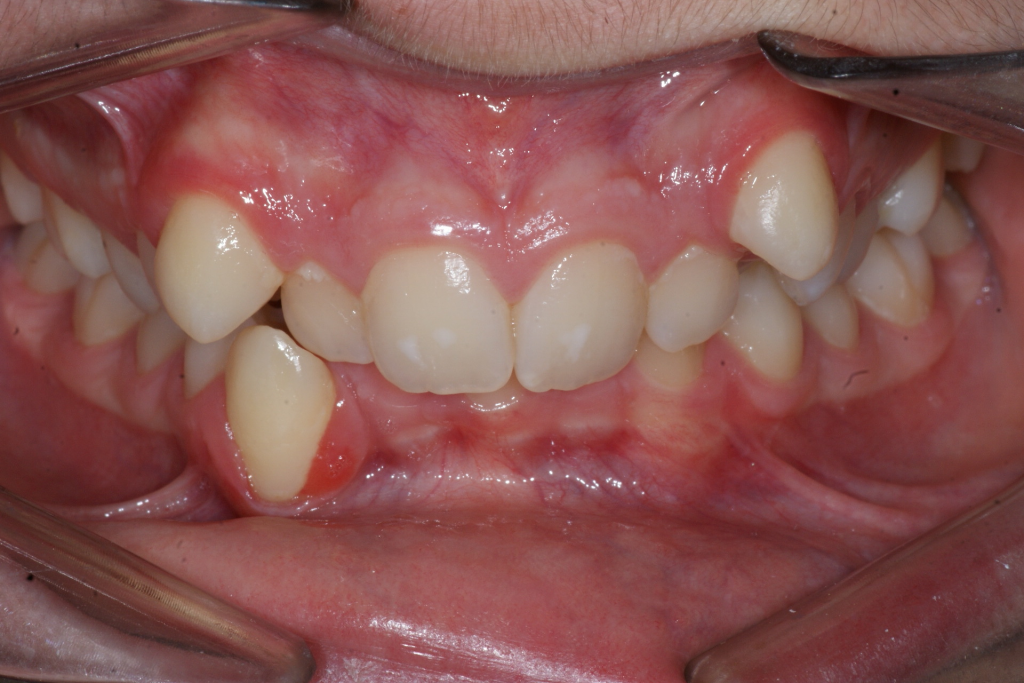

Correction d’une malocclusion de type Classe II avec chevauchement sévère aux 2 arcades. Des appareils fixes (boîtiers), une expansion palatine et l’extraction de 4 prémolaires (#14-24-35-45) furent nécessaires pour améliorer ce sourire. Traitement chez un adolescent, réalisé en 28 mois.